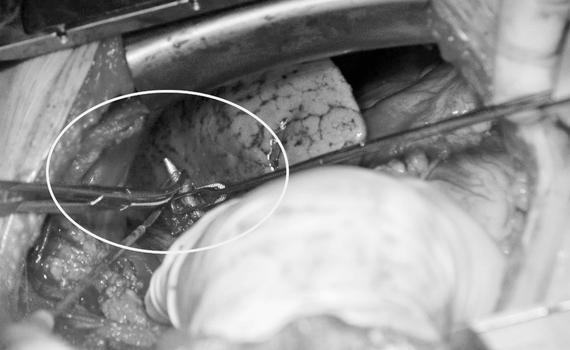

Коварство пятисантиметровой пули остановлено кардиохирургами госпиталя Вишневского